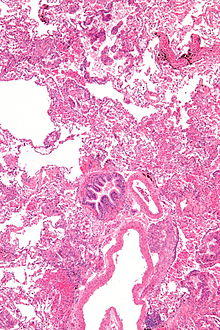

Micrograph of lymphangioleiomyomatosis. H&E stain.

Pathology

Grossly, LAM lungs are enlarged and diffusely cystic, with dilated air spaces as large as several centimeters in diameter.[105][106] Microscopic examination of the lung reveals foci of smooth muscle-like cell infiltration of the lung parenchyma, airways, lymphatics, and blood vessels associated with areas of thin-walled cystic change. LAM lesions often contain an abundance of lymphatic channels, forming an anastomosing meshwork of slit-like spaces lined by endothelial cells. LAM cells generally expand interstitial spaces without violating tissue planes but have been observed to invade the airways, the pulmonary artery, the diaphragm, aorta, and retroperitoneal fat, to destroy bronchial cartilage and arteriolar walls, and to occlude the lumen of pulmonary arterioles.[105]

There are two major cell morphologies in the LAM lesion: small spindle-shaped cells and cuboidal epithelioid cells.[107] LAM cells stain positively for smooth muscle actin, vimentin, desmin, and, often, estrogen and progesterone receptors. The cuboidal cells within LAM lesions also react with a monoclonal antibody called HMB-45, developed against the premelanosomal protein gp100, an enzyme in the melanogenesis pathway.[107] This immunohistochemical marker is very useful diagnostically, because other smooth muscle–predominant lesions in the lung do not react with the antibody.[108] The spindle-shaped cells of the LAM lesion are more frequently proliferating cell nuclear antigen positive than the cuboidal cells, consistent with a proliferative phenotype.[107] Compared with cigar-shaped normal smooth muscle cells, spindle-shaped LAM cells contain less abundant cytoplasm and are less eosinophilic. Estrogen and progesterone receptors are also present in LAM lesions,[109][110][111] but not in adjacent normal lung tissue.[112] LAM lesions express lymphatic markers LYVE-1, PROX1, podoplanin and VEGFR-3. The smooth muscle–like cells of AMLs are morphologically and immunohistochemically similar to LAM cells, including reactivity with antibodies directed against actin, desmin, vimentin, and HMB-45 as well as estrogen and progesterone receptors.[113][114] Unlike the dilated airspaces in emphysema, the cystic spaces found in LAM may be partially lined with hyperplastic type II cells.[115]